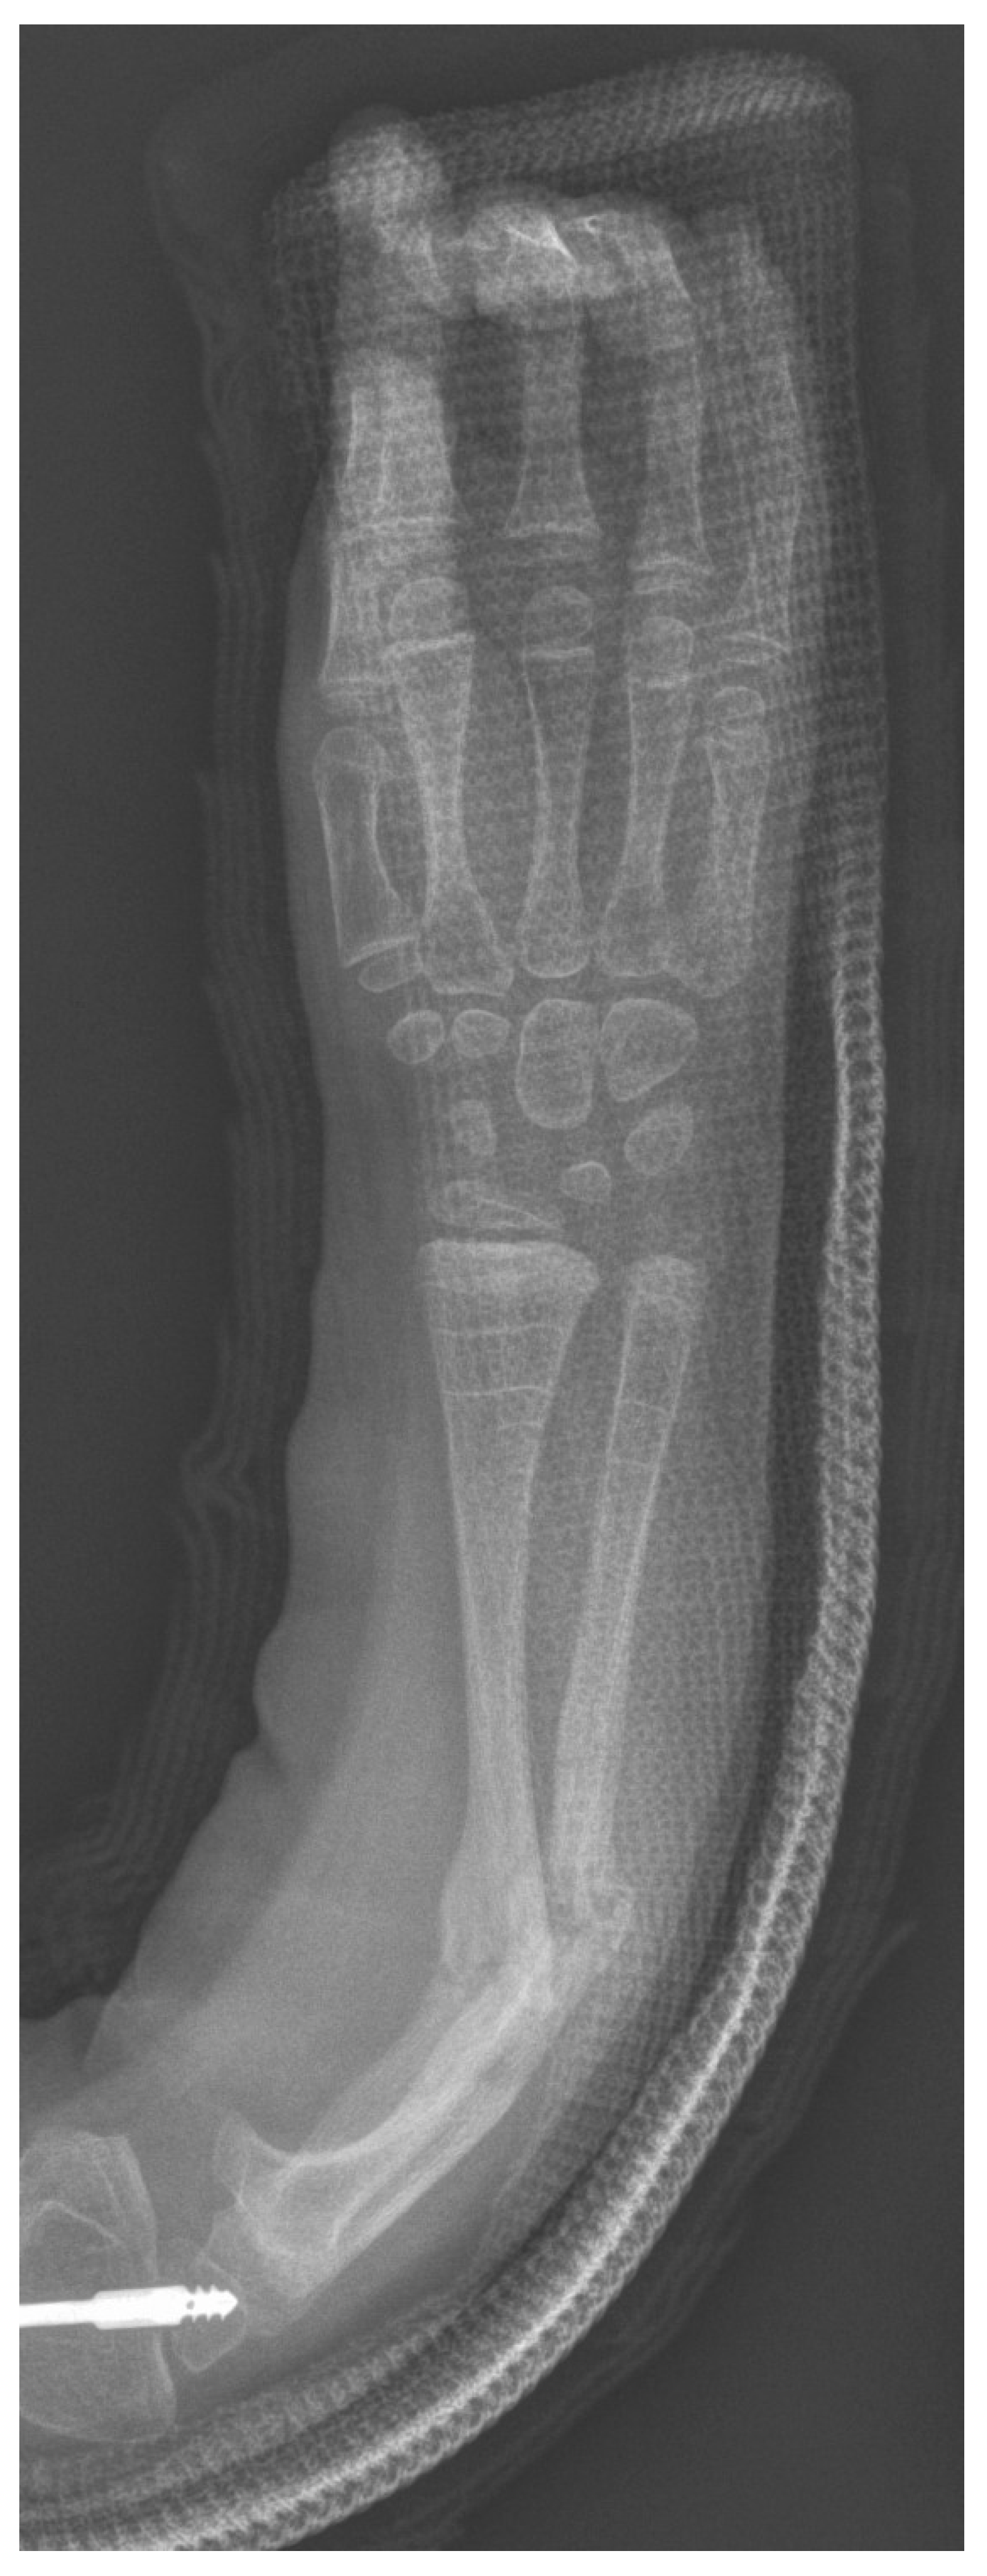

The indication for surgery in all children was deformity with recurrent fracture and loss of motion interfering with function (Figure 1). Surgical treatment of the forearm bones was discussed with families when the children were experiencing multiple radius and/or ulna fractures that resulted in bowing of the forearm that resulted in difficulties with function. All surgeries were performed by the senior author. Forty-eight total bony procedures on 18 patients were performed with 9 patients having only one forearm corrected and 9 having both forearms corrected. In total, 29 total procedures were performed on the right (14 forearms) and 19 total procedures on the left (13 forearms). Fourteen patients are right-hand dominant, 1 is left-hand dominant, and 3 do not have hand dominance recorded in the chart. Bilateral forearm surgery was performed in separate operative trips for all except one patient whose mother requested that we treat both forearms in the same operative setting. If there were recent fractures, we attempted to percutaneously pass a k-wire in the radius or ulna as we manually corrected the deformity. If this was deemed unsafe, or if an osteotomy was needed to correct the deformity, we opened at the apex of the deformity and attempted to perform one osteotomy. We routinely performed this with a rongeur, passing a separate wire into the next segment before passing the wire across the osteotomy site. If the deformity could not be corrected fully we performed a second osteotomy. The ulnar wire was placed across the olecranon apophysis to protect the entire ulna down to the distal ulnar physis. The radial wire was placed through the radial styloid across the distal radial physis up to the proximal radial physis to protect the entire radius. The radius was typically approached through the anterior volar approach, with exceptions when dorsal or radial approaches were performed depending on the apex and severity of the radial bow. When the radius has significant bowing present, it was often subcutaneous, and the approach can be safer and more direct to approach it in a non-standard direct manner. Figure 2 shows typical preoperative deformity and postoperative healed osteotomies over 5 years. Post operatively patients were placed into a sugar tong splint for 4 weeks after surgery. Postoperative X-rays were performed at 4 weeks, and patients were then transitioned to a removable splint for an additional 3–4 weeks.

Figure 1. A 4-year-old female with Type III OI with typical appearing recurrent fractures and deformity of the forearm.